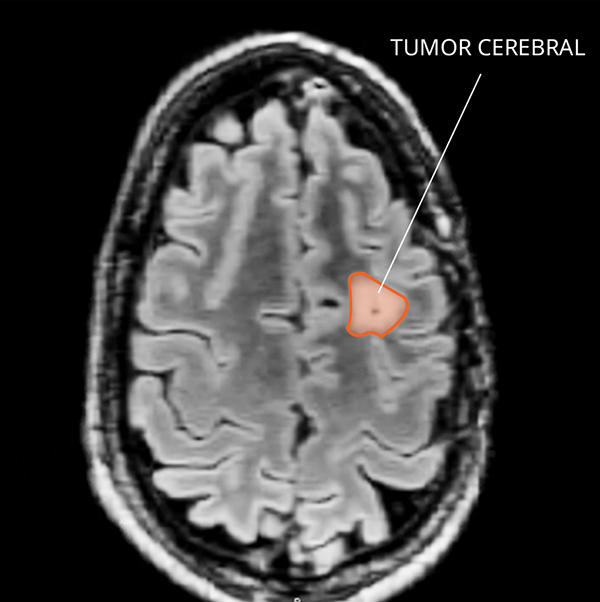

Imagen por resonancia magnética (IRM) de un xantoastrocitoma en el cerebro.

¿Cómo se ven un XAP y un XAP anaplásico en las imágenes por resonancia magnética?

El XAP suele formar quistes en los que se acumula líquido en un nódulo parietal, lo que significa que hay un quiste dentro del tejido sólido de aspecto denso en la IRM. El XAP anaplásico se puede ver como un XAP, pero como la forma de ambos varía, es difícil diferenciarlos de otros tumores primarios del SNC. No es posible diagnosticar el XAP o el XAP anaplásico solo mediante el uso de imágenes porque estos tumores a veces tienen el mismo aspecto que los glioblastomas y otros cánceres del cerebro de grado alto.